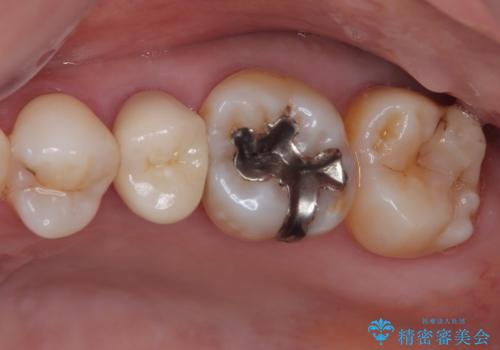

- むし歯と銀歯を気にして来院された患者様です。

銀歯の歯は既に根管治療がされており、根尖部に病変が認められないため、根管治療を行うことなくオールセラミッククラウンにて補綴治療を行うこととしました。

むし歯の症状のある歯は、ややしみることがある程度でしたが、レントゲン写真では非常にむし歯が大きく、神経組織に迫っている状態でした。

術前診査では神経を全て取る可能性は低いと予想されましたが、一部切除する可能性があることを伝えた上で治療を行うこととしました。

やはりむし歯は大きく、一部歯髄を切除することとなりましたが、その後は良好な経過をたどっています。